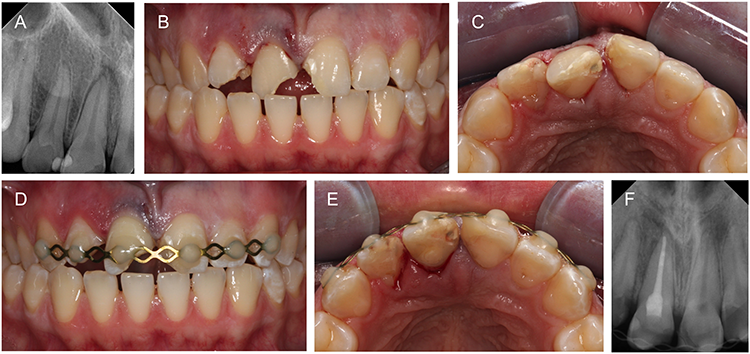

Pathologie und Management von Wurzelresorptionen

Bei der zahnärztlichen Routineuntersuchung oder im Rahmen einer professionellen Zahnreinigung treten oft unerwartet Wurzelresorptionen an bleibenden Zähnen zutage. Sie zeigen sich klinisch als tastbare Läsionen oder ungewohnte Defekte auf Röntgenaufnahmen. Dabei ist häufig unklar, worin die Ursache pathologischer Resorptionen liegt, welche Behandlungsschritte notwendig sind und warum bleibende Zähne normalerweise nicht resorbiert werden.

Pulparegeneration in der Praxis: „Pulp Fiction“?

Einem Zahn mit nekrotischer Pulpa neues Leben einzuhauchen, das ist das Ziel der regenerativen Endodontie. Es handelt sich um ein Forschungsfeld, das momentan vielerorts Aufmerksamkeit auf sich zieht. Dieser Artikel soll einen kurzen Überblick über den Stand der Forschung und die tatsächliche Umsetzbarkeit dieses Unterfangens geben.